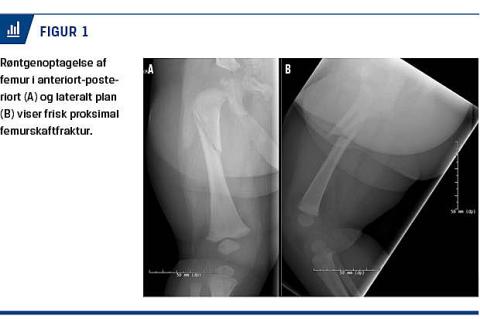

En tre måneder gammel pige blev set primært af egen læge pga. gråd og uro igennem et døgn. Det blev desuden bemærket, at der var irritation i det ene øje, og at hun trak højre ben til sig ved berøring. Pigen og forældrene blev sendt hjem. Dagen derpå kontaktede forældrene vagtlægen, idet hun fortsat var urolig og havde fået feber. Der havde ikke været et erkendt traume. Hun blev indlagt på en børneafdeling på mistanke om urinvejsinfektion. På grund af normale biokemiske forhold og en normal urinprøve blev diagnosen afkræftet. Under indlæggelsen var hun afebril, og der var lagt op til udskrivelse. Det blev dog bemærket, at højre ben føltes varmere og lidt mere spændt end det kontralaterale. Derfor blev der foretaget ultralydskanning af hofterne på mistanke om coxitis simplex. Dette gav mistanke om fraktur i femur. Diagnosen, en frisk femurfraktur, kunne bekræftes ved røntgenoptagelser i to planer (Figur 1A). De sædvanlige ledsagende undersøgelser, herunder undersøgelse af totalskelettet, blev foretaget, og der kunne ikke påvises andre skader. Der blev foretaget underretning, og hun blev overflyttet til en ortopædkirurgisk afdeling med henblik på strækbehandling og anlæggelse af hoftespica. Behandlingen blev afsluttet to uger efterfølgende, hvor en røntgenoptagelse viste helet fraktur med callus (Figur 1B). Konklusivt blev mistanken om battered child syndrome (BCS) afvist.

Diagnosen stilles som regel let ved røntgenoptagelse af femur i to planer (Figur 1A). Indikationen for et røntgenbillede kan dog være sværere at stille, særligt når anamnesen er sparsom. Her er det vigtigt at forstå barnets smertereaktion, f.eks. at det trækker benet til sig, som barnet i sygehistorien gjorde. Desuden bør man være opmærksom på de beskrevne objektive fund. Man skal give sig god tid til at undersøge benene, idet hævelsen kan være lille pga. ekstremitetens lille størrelse. Herudover skal man være særlig opmærksom på palpationen af lårene, idet blødningen fra frakturen, vil medføre spændte lår. Misfarvningen ses ikke altid i den akutte fase.